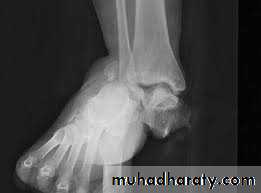

Calcaneal fracture, also known Don Juan fracture, is a fracture of the calcaneus. It is usually caused by a fall from height when one lands on their feet. These fractures represent approximately 2% of all fractures but 60% of tarsal bone fractures.